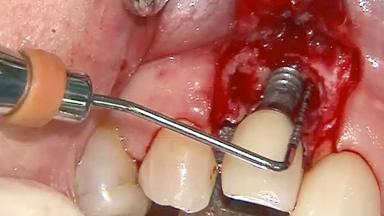

This case describes both a surgical and an anti-infective approach for the management of peri-implantitis, including treatment of the entire dentition to eliminate any deep periodontal pockets that could serve as reservoirs for bacterial re-colonization at the implant site. A 65-year-old female patient was referred to the periodontist in 2013 for assessment and management of an infection at implant 12. On examination, probing depths at implant 12 were 11 mm with suppuration and bleeding on probing.